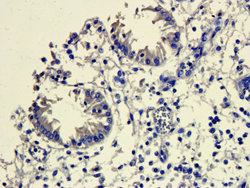

- Submitted by

- antibodies-online (provider)

- Main image

- Experimental details

- IHC